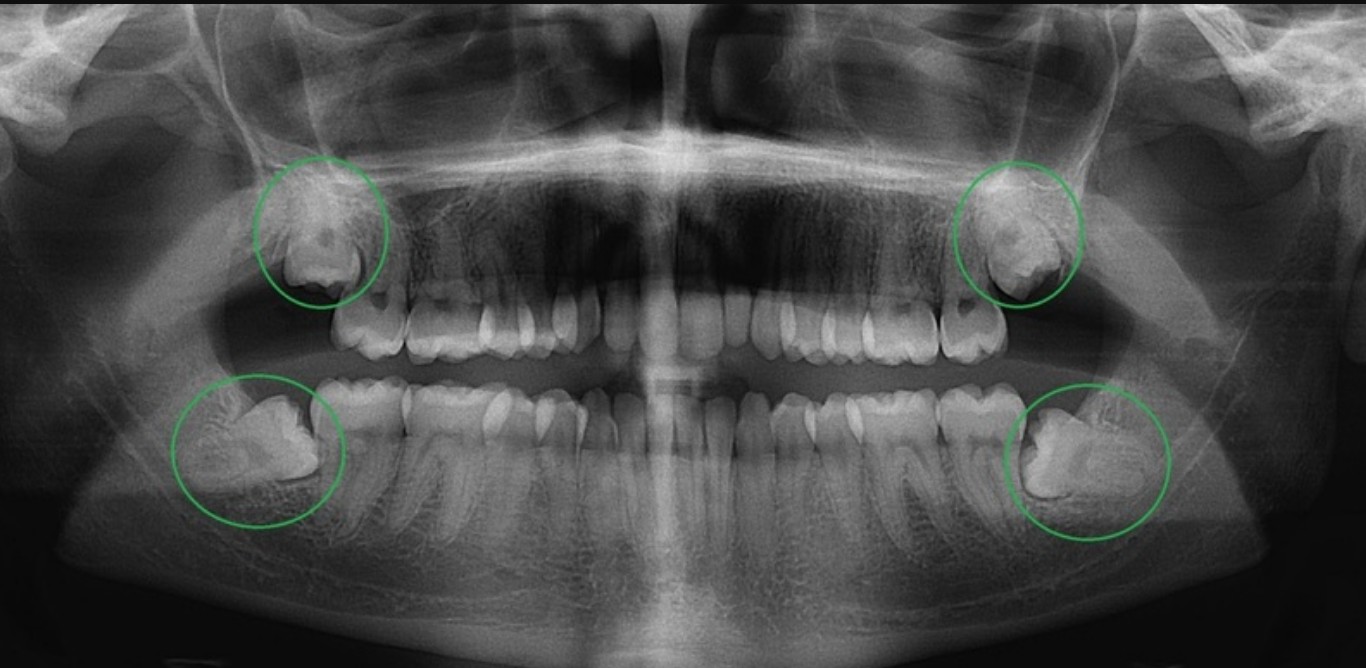

Nhổ răng khôn khó và nguy hiểm nhất là ở vị trí nào? https://yentamsongkhoe.com/nho-rang-khon-kho-va-nguy-hiem-nhat-la-o-vi-tri-nao-2926/ https://yentamsongkhoe.com/nho-rang-khon-kho-va-nguy-hiem-nhat-la-o-vi-tri-nao-2926/#respond Tue, 11 Nov 2025 03:17:34 +0000 https://yentamsongkhoe.com/?p=2926 Răng khôn (hay còn gọi là răng hàm số 8, tiếng Anh là wisdom teeth) là những chiếc răng mọc cuối cùng trên cung hàm, thường xuất hiện trong độ tuổi từ 17–25. Việc mọc răng khôn đôi khi diễn ra bình thường, nhưng trong phần lớn trường hợp, chúng mọc lệch, mọc ngầm hoặc chen chúc, gây đau nhức, viêm nhiễm, thậm chí làm ảnh hưởng đến cấu trúc răng kế cận.

Răng khôn có thể mọc ở hai vị trí chính:

• Răng khôn hàm trên (răng số 8 trên): nằm ở phần cuối của xương hàm trên, gần xoang hàm.

• Răng khôn hàm dưới (răng số 8 dưới): nằm sâu ở cuối cung hàm dưới, gần ống thần kinh huyệt răng dưới.

• Mọc ngầm: răng khôn bị bao bọc hoàn toàn trong xương, không lộ ra ngoài nướu.